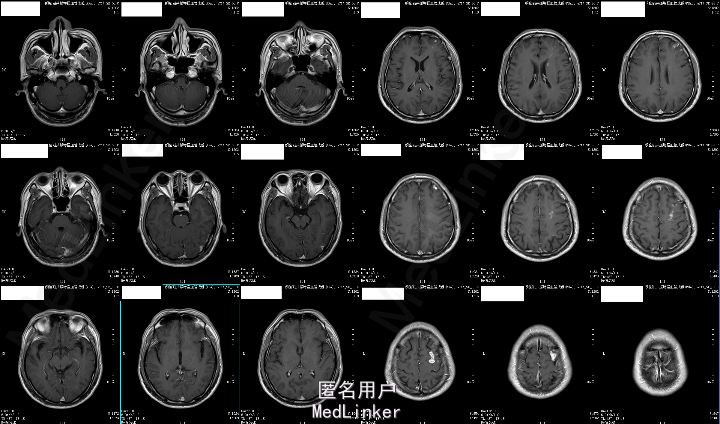

2015-05-26外院头颅MR:1.左额叶、枕叶病变考虑感染性病变可能性大(曼氏裂头蚴感染?)2.双侧上颌窦、筛窦慢性炎症。

2015-6-01我院头颅MRA:1.左侧额叶、枕叶及左侧基底节尾状核多发异常信号,考虑寄生虫感染(曼氏裂头蚴感染?)可能性大;2.左侧大脑前动脉A1段起始部稍狭窄;3.双侧筛窦炎症。

患者今年4月份时有吃“田螺、黄鳝”病史,既往有“高血压、糖尿病”,未规律治疗,结合其临床表现及头颅MRA“钻隧道”样改变,目前考虑“曼氏裂头蚴感染”可能性大。

成的中枢神经系统寄生虫病。I临床较为少见,易误诊。一般认为感染该病的途径有以下几种:食生或半生的蛙肉、蛇肉等(含裂头蚴);带有伤口的皮肤敷贴感染的生蛙皮、蛙肉等;饮用了含剑水蚤的生水。脑裂头蚴病的临床表现因感染部位的不同而各异。多以头痛、癫痫大发作及肢体活动障碍等为主,严重者可致颅内高压、视力损害、意识障碍甚至突然死亡。脑脊液检查可有蛋白及细胞数轻度升高。儿童脑裂头蚴病的病程一般不长,有些因虫体的迁延,其症状和体征也会发生改变。该病影像学表现多为单侧受累的单发病灶。病灶多位于皮质,也可侵犯脑室、脑干和小脑。活的虫体在脑内活动形成隧道、虫体分泌的产物及虫道周围的炎性反应使得该病影像学上具有一定特点:(1)主病灶一般较小,直径小于2 cm;(2)局部常伴发炎性反应,病灶周围脑实质可见不规则大片状水肿影;(3)MRI检查多表现为混杂长T1、长T2信号,临近侧脑室可变大,即所谓的“负效应”,增强扫描可见病灶呈匍行管状、串珠状、绳结状、扭曲条索状强化;(4)不同时期的影像学检查,病灶可在不同的部位;(5)CT检查可见点状钙化影,虽脑MRI对于钙化的显影不如CT,但也可表现出不均匀信号。脑裂头蚴病的病理学表现具有一定特点,裂头蚴幼虫在脑内迁徙游走形成坏死隧道,同时释放蛋白酶毒素溶解周围组织引起炎性反应,周围脑组织坏死后,局部炎性细胞浸润和纤维胶质细胞增生形成炎性肉芽肿。肉芽肿内可见有一条或数条虫体,虫体不分节,实体、无体腔,具有特征性的体壁结构是散在分布的椭圆形石灰小体及束状纵行肌纤维,前者可能为虫体的残骸。裂头蚴抗体血清免疫学检查(ELISA法)具有高度的特异性和敏感性。手术摘除裂头蚴为该病最有效的治疗手段,可